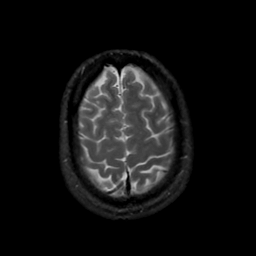

MR Study #22, December 1, 1991 -- Slice #42